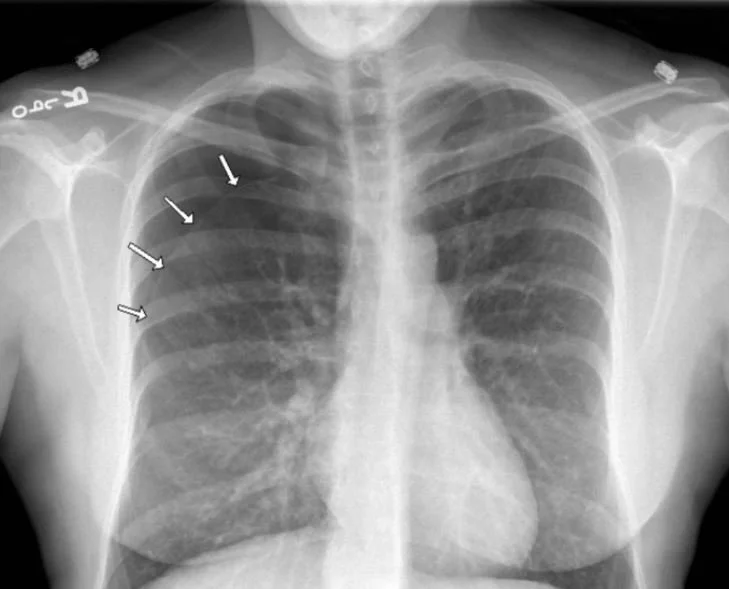

Our patient had lymphangioleiomyomatosis (LAM).  This is a rare cystic lung disease that occurs mainly in young women in childbearing years.  It is rare,  but 50% of patients present with pneumothorax  resulting in presentations for emergency care. It is often found in association with tuberous sclerosis complex(TSC) and is a congenital defect associated with TSC1 and TSC2 gene mutations. These mutations lead to dysregulation of the rapamycin (mTOR) signaling pathway resulting in unchecked muscle cell growth in the lung.  This leads to air trapping, creating thin-walled cysts that can rupture.

If you included catamenial pneumothorax  in your differential you would also be correct. Pneumothorax is a common presentation of thoracic endometriosis. It occurs within 72 hrs of menstruation and accounts for 3-6% of spontaneous pneumothorax cases in women of childbearing age.